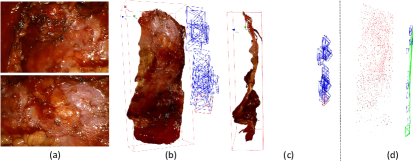

In order to evaluate the quantified accuracy of our 3D reconstruction method, we used the CT imaging of tissues as the gold standard. In this experiment, CT scans of four ex-vivo porcine livers and three kidneys were obtained (Siemens Somatom, Erlangen Germany) with a 0.6 mm resolution at our hospital, and we used the 3D Slicer software to segment the tissue models from the CT images, as shown in Fig. 9. We captured stereo videos of the tissues with the KARL-STORZ stereo laparoscope, the details of which are in Tab. II. Surfaces of livers and kidneys are very smooth and have low textures, but the proposed method was still able to reconstruct the 3D models, as shown in Fig. 7. To quantify accuracy, we registered the 3D reconstructed model with the CT segmentation results by first manually selecting landmarks, such as tissue tips, edge points and other recognizable points, and then refining the registration with the ICP algorithm. As shown in Fig. 7 (a), the root mean square errors (RMSE) with the liver cases are 1.3, 1.1, 1.4 and 2.0 mm respectively. The fourth liver case has a relatively larger error because we used an entire piece of liver and the video was captured at a larger camera-tissue distance. The results on porcine kidneys are shown in Fig. 7 (b), the RMSE of which are 1.0, 1.0 and 1.1 mm respectively. The histograms of errors are also provided in Fig. 7, which show that most points have an error of less than 2mm. It is worth noting that there are multiple sources of errors, including 3D reconstruction error, CT resolution error, CT segmentation error and registration error that contribute to the obtained RMSE in this experiment. In addition, because the livers and kidneys were placed on a textureless plastic sheet and part of the sheet were also included in the 3D reconstructed model, which is difficult to be totally removed (see the tissue edges in the distance maps of Fig. 7), so the quantified error may also include a small amount of the background. Therefore, it is a reasonable assumption that the actual error of our 3D reconstruction method is smaller than the reported RMSE.